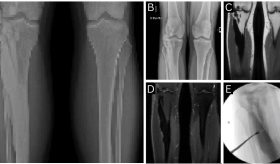

Según lo explica el Dr. Hernández, con los tratamientos tradicionales, lo que hacían era colocar unas prótesis que lamentablemente tienden a obstruirse, ya sea porque el tumor crece dentro de las prótesis o porque se obstruyen por contenido del drenaje de hígado.

Por lo cual, "con este tipo de alternativas que nos brinda la radiofrecuencia, se aumenta es la permeabilidad del drenaje biliar y eso les da mejor calidad de vida, de hecho, algunos trabajos han mostrado mayor sobrevida en estos pacientes" explicó el Dr. Geovanny.